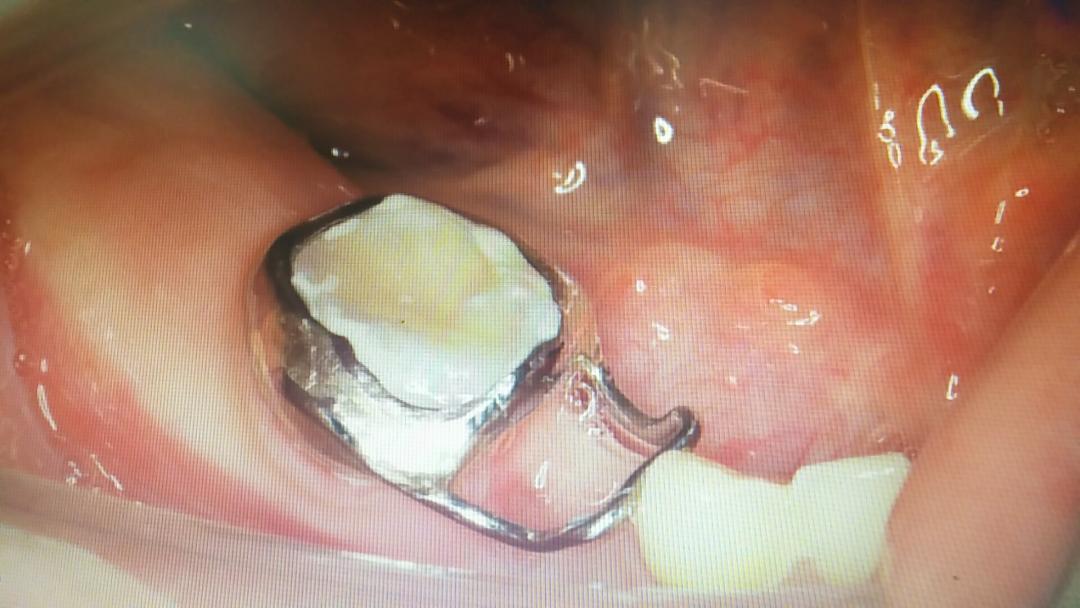

一般乳牙缺失时,医生可以帮孩子做一个间隙保持器,保持空间,等待恒牙萌出。

间隙保持器